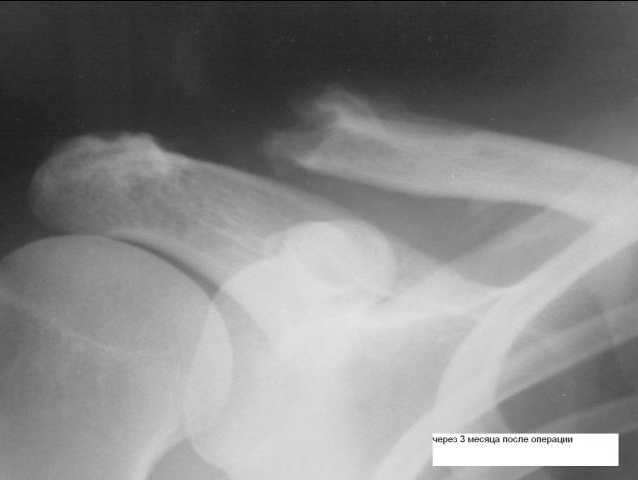

Здравствуйте, уважаемый Роман! Прежде, чем обсуждать дальнейшую тактику, хотелось бы выяснить, чем пациентка мотивирует желание повторно оперироваться. Что её не устраивает: косметический дефект или нарушение функции? Чего она ожидает от операции? Улучшить то, что сейчас имеется, вряд ли получится. Сравните послеоперационные рентгенограммы с последними. Сделайте рентгенограммы с нагрузкой (груз 5 кг привязать к нижней трети предплечья - не держать в руке!). Тогда можно будет определиться, лопаточно-ключичная диссоциация рецидивировала или не была устранена. Есть нестабильность ключицы, вызывающая боли - оперировать (только не акромиально-ключичная фиксация!). По моему мнению, методикой выбора может стать моделирующая резекция ключицы с замещением клювовидно-ключичной связки доступным методом (аутосухожилие, широкая фасция, синтетический имплант). Продумать программу реабилитации в зависимости от выбранной методики. Если нестабильности нет, болевой синдром не выражен - оставить как есть, объяснить пациентке, что косметический эффект будет условным, а вот риск осложнений высок (кто возьмет на себя смелость с уверенностью сказать, что там на месте лизированного акромиального конца ключицы и что произошедшее есть на 100% асептический процесс). С уважением, Константин Деданов, Челябинск